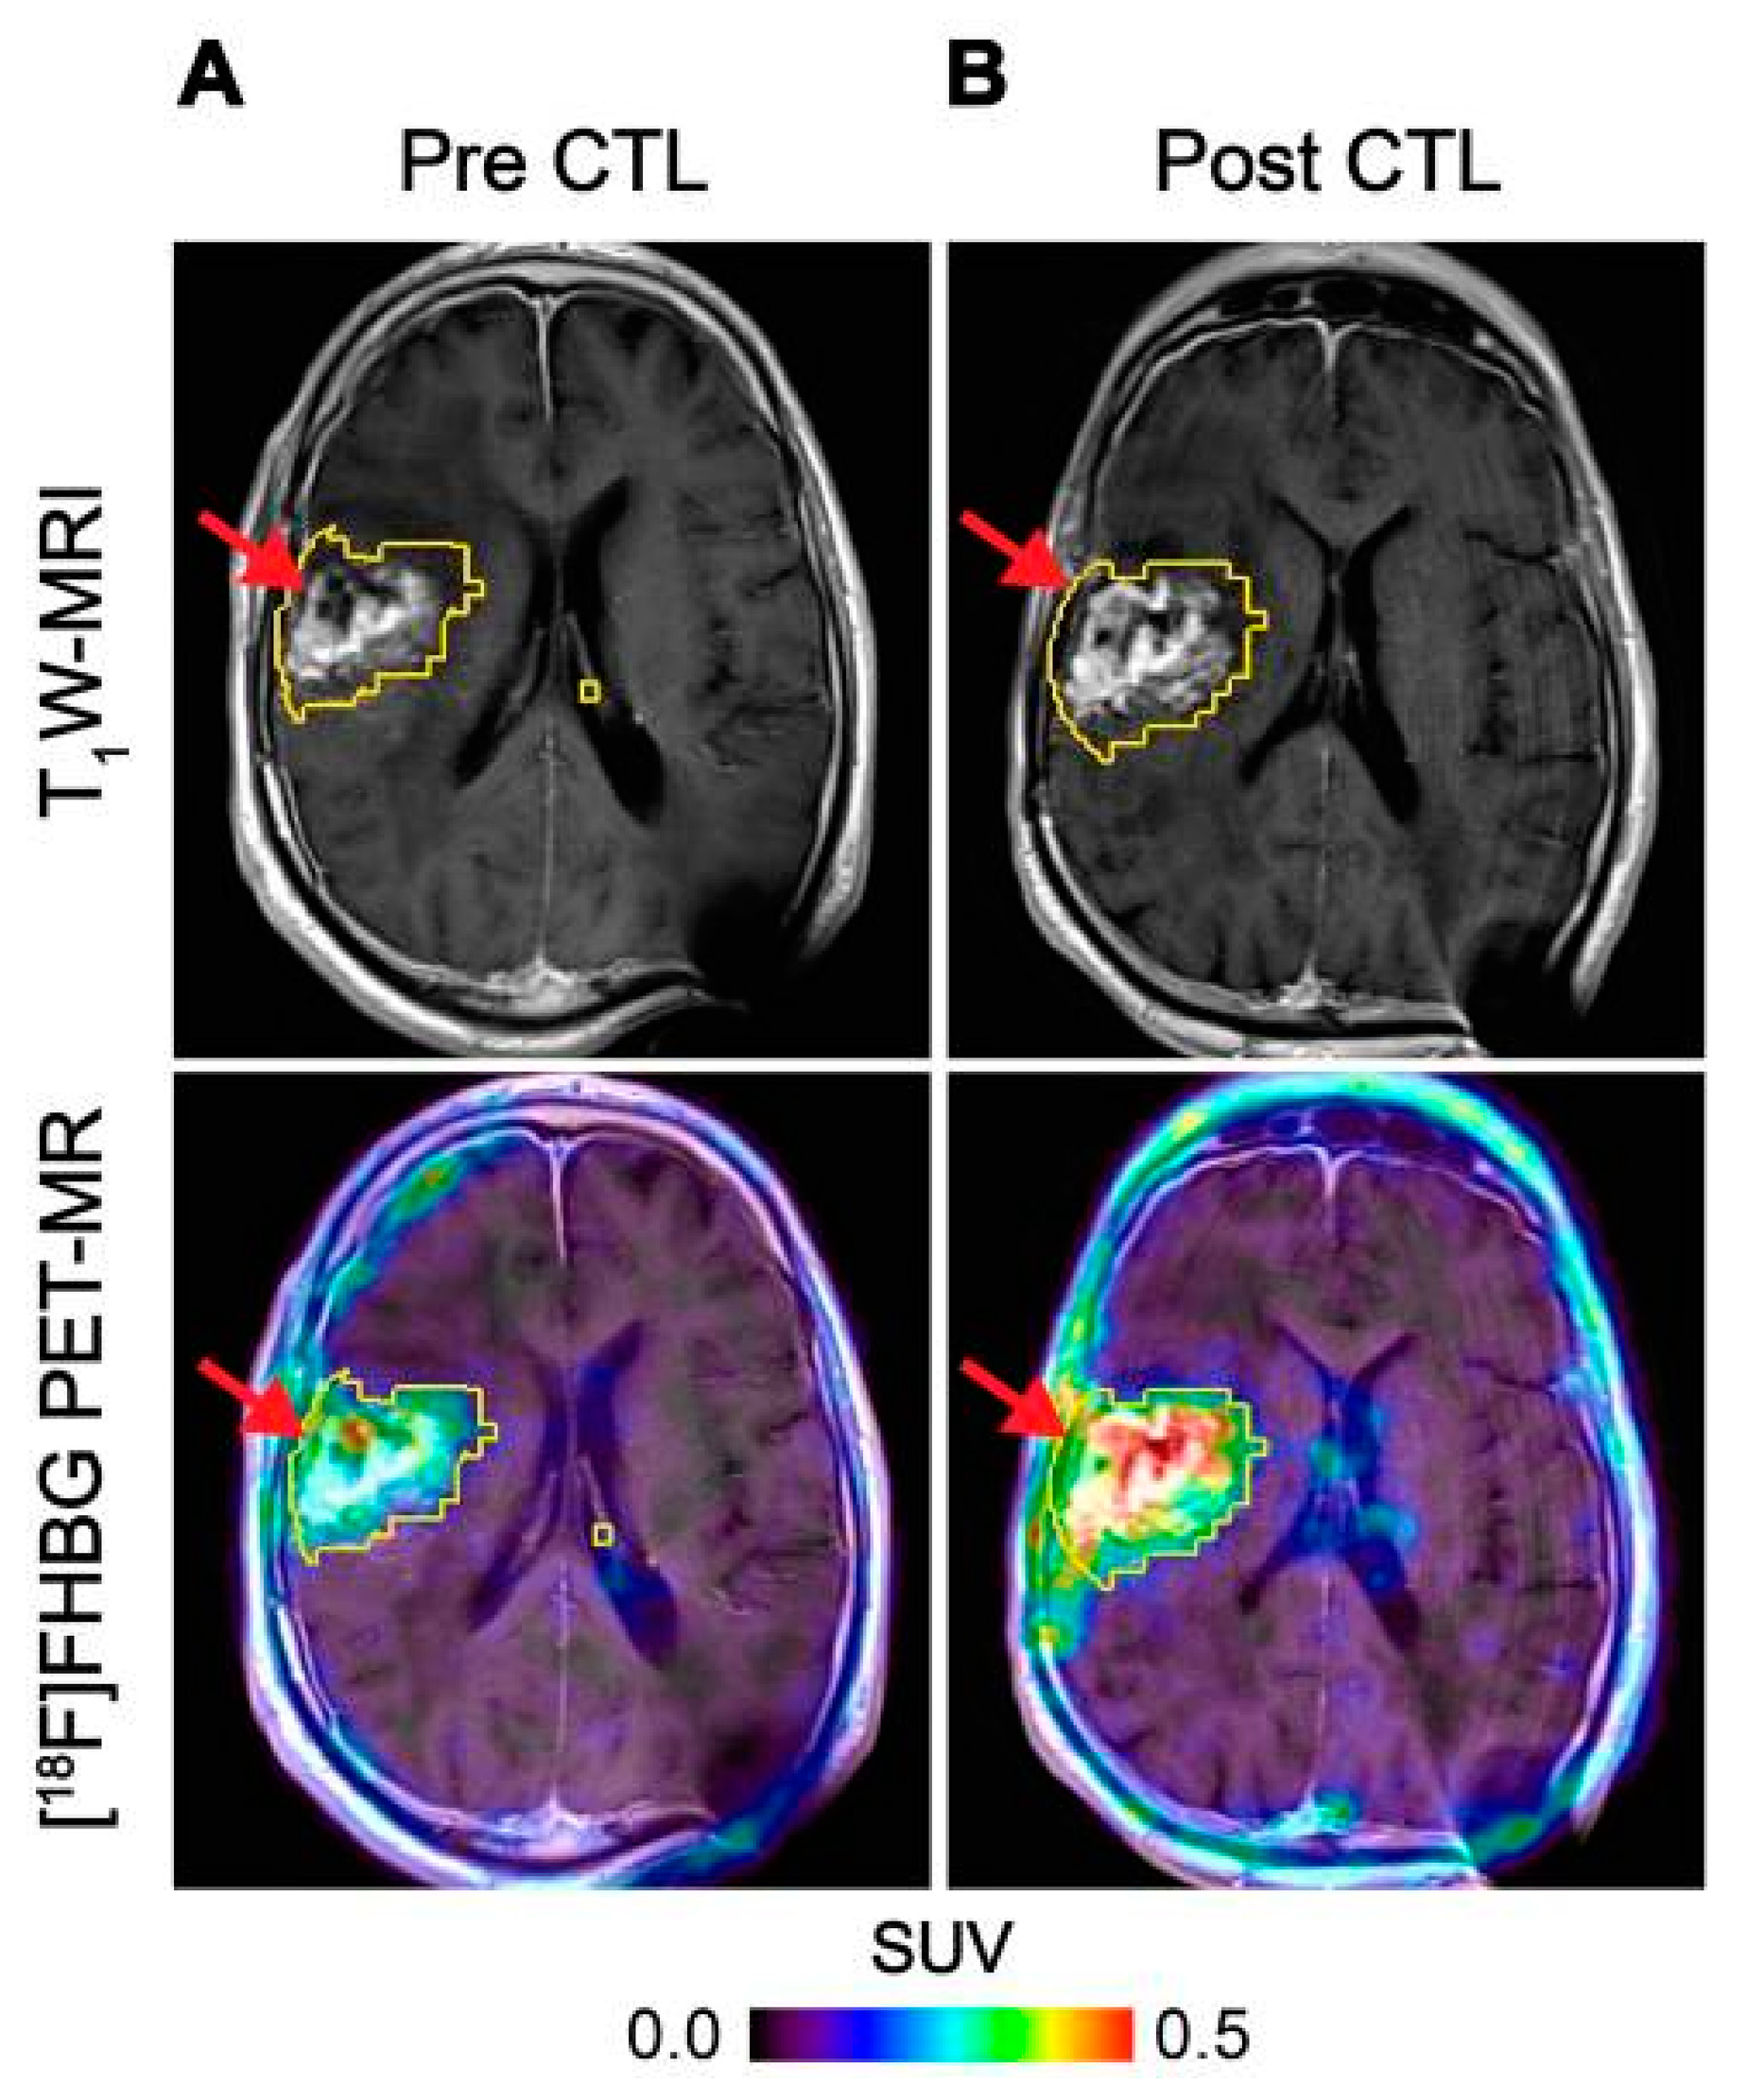

Figure 3.

Imaging of HSV1-tk gene reporter expression in genetically modified CTLs with [18F]FHBG. [18F]FHBG-PET imaging was performed in a patient with recurrent glioblastoma multiforme tumour in the right frontoparietal lobe before (A) and 1 week after (B) CTL infusions. Allogeneic CTLs and IL-2 were injected intratumorally (red arrows). Tumour recurrence was monitored by T1-weighted (T1W) MRI (top panels) and [18F]FHBG-PET images were fused with the MR images (bottom panels). A significant increase in [18F]FHBG uptake and PET signal was detected following CTL infusion, which was likely to be due to CTL cell trafficking. Figure reproduced from [51].